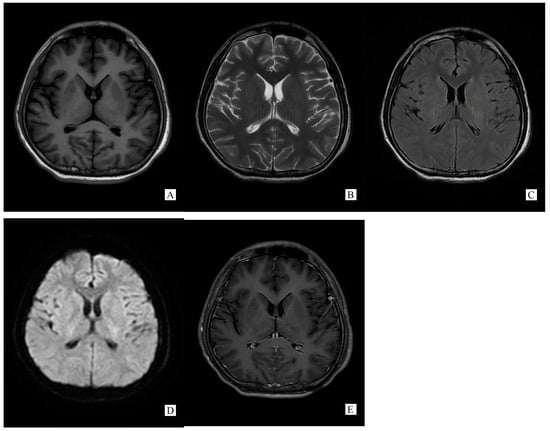

Figure 2.

(Performed on 13 November 2021) SCC lesion totally disappeared on brain MRI ((A). T1WI, (B). T2WI, (C). T2 flair, (D). DWI, (E). Post-gadolinium T1-weighted).

A repeated spinal tap was performed on 11 November 2021, which showed increased intracranial pressure, CSF glucose was still below normal contents, while CSF protein and chloride was lower than before and still abnormal (ICP 330 mmH2O, Glu 2.14 mmol/L, Cl− 119.50 mmol/L, Pro 1.05 g/L). WBC counts increased to 500 × 106/L. CSF screen using next-generation sequencing (NGS) indicated no infection. The CSF test of neural auto-antibodies revealed positive anti-GFAP antibodies (antibody titer 1:32), while the serum test was negative. CSF Ig electrophoresis revealed positive IgG oligoclonal bands (≥2 bands). A second cerebral MRI was performed on 13 November 2021 showing totally disappeared on SCC lesion (Figure 2).

Generally, typical features of autoimmune GFAP astrocytopathy present as a linear, radial perivascular enhancement pattern on brain MRI, and central longitudinally extensive enhancement pattern on spinal cord MRI [7]. RESLES is typically classified into two patterns on MRI: type I is an isolated lesion on SCC, type II is a lesion in SCC expending to callosal fibers, cerebral white matters or anterior portion of corpus callosum. No matter type I or type II, lesions can be significantly shrunk or totally disappeared within a month, accompanied with the relief of symptoms [8]. In the MRI of our case, the lesion was located in the SCC, manifested a hypointense signal on T1WI and hyperintense on T2WI and DWI, reversibly, which is similar to type I RESLES, but unlike the typical autoimmune GFAP astrocytopathy.